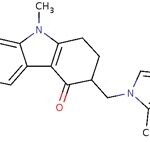

érythromycine

L’érythromycine est un antibiotique du groupe des macrolides.